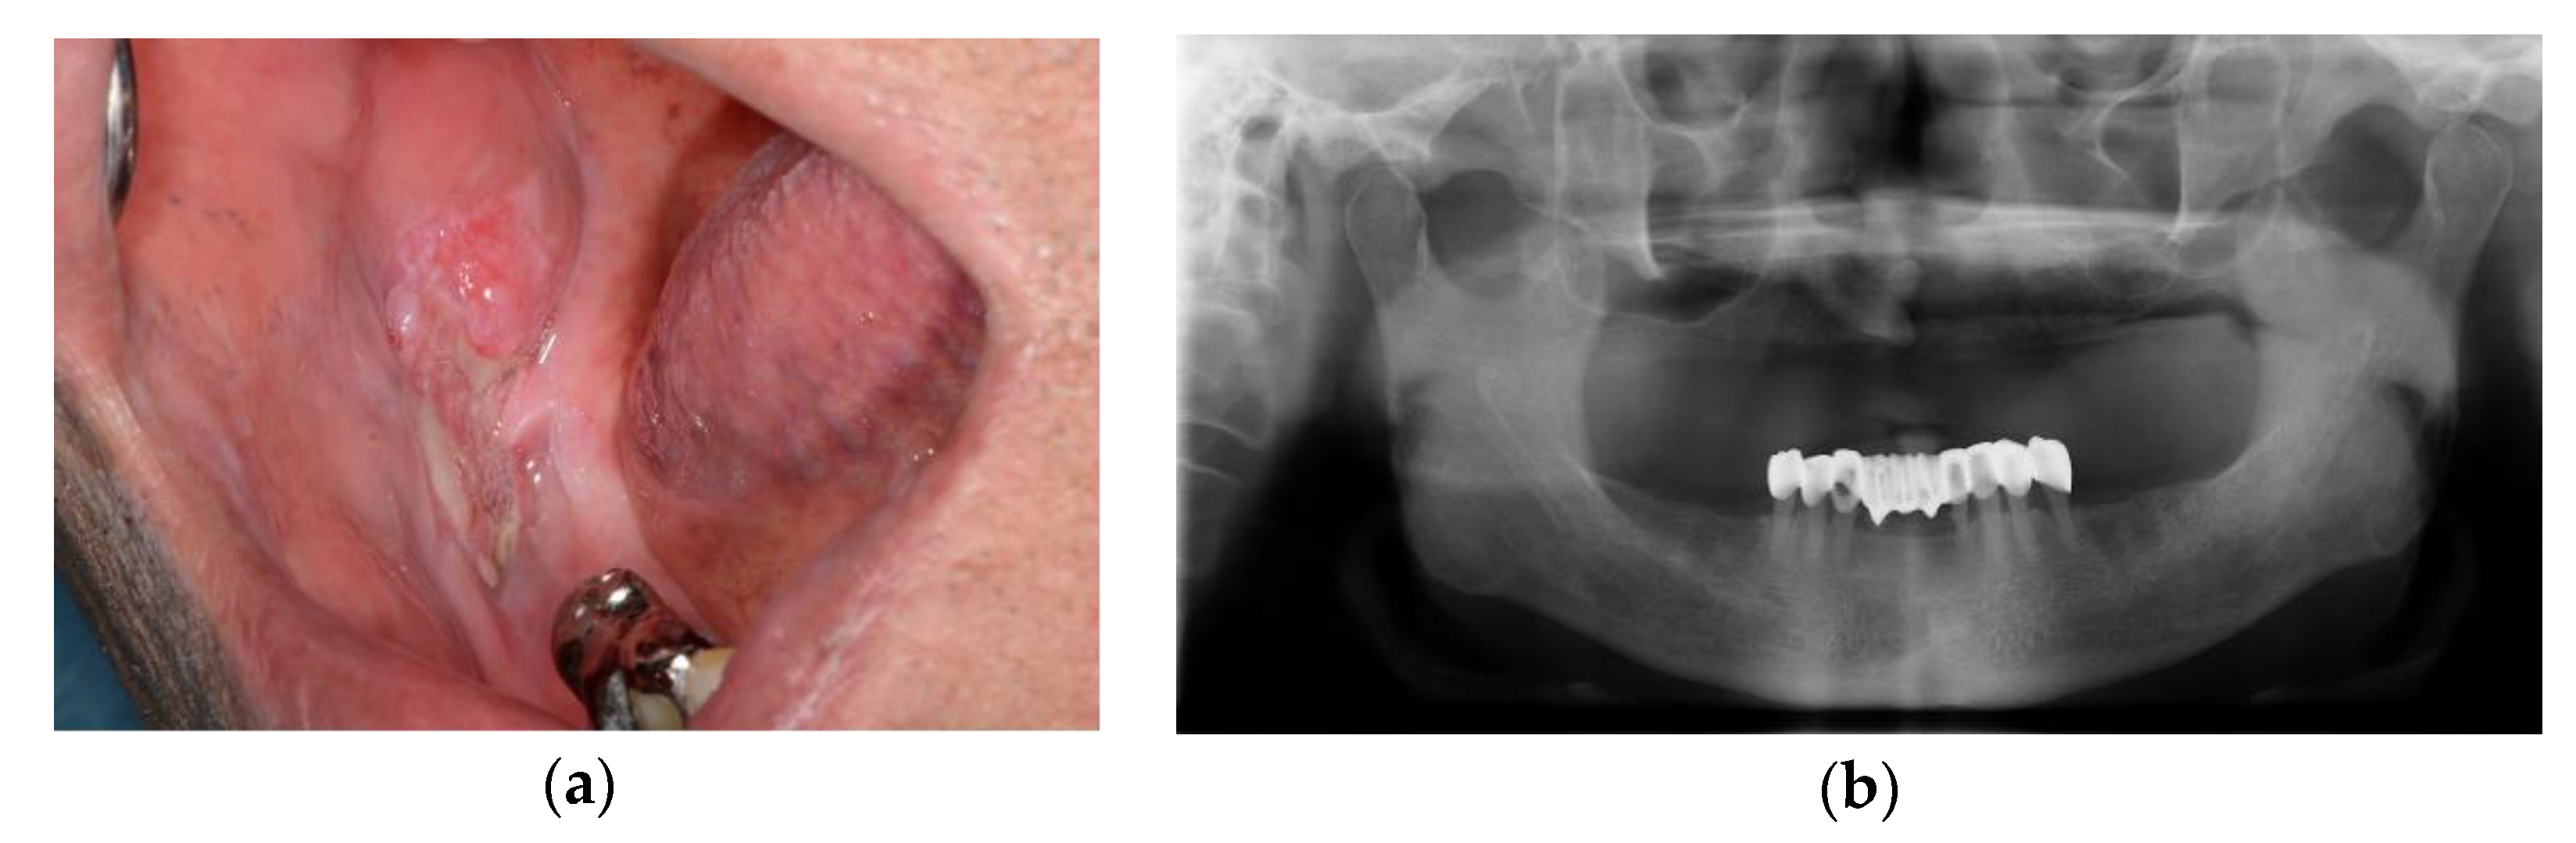

A 70-year-old male presented at the department of oral and maxillofacial surgery with the complaint that the right lower gingiva was not healed (Figure 1).

Figure 1.

Initial examinations: (a) intraoral photograph showed the granulomatous lesion on right lower gingiva; (b) no bone invasive lesion was seen in the panoramic view.

Incisional biopsy results were diagnosed as SCC. CT and PET-CT were taken. The lesion was confined to soft tissue and lymph nodes in the right submandibular node, with intense fluorodeoxyglucose (FDG) uptake observed on the radiological images. Therefore, marginal mandibulectomy and selective neck dissection (I–Ⅲ) were planned for the management of the SCC, and a DCIA-based iliac crest flap was planned to reconstruct the resected mandibular site.